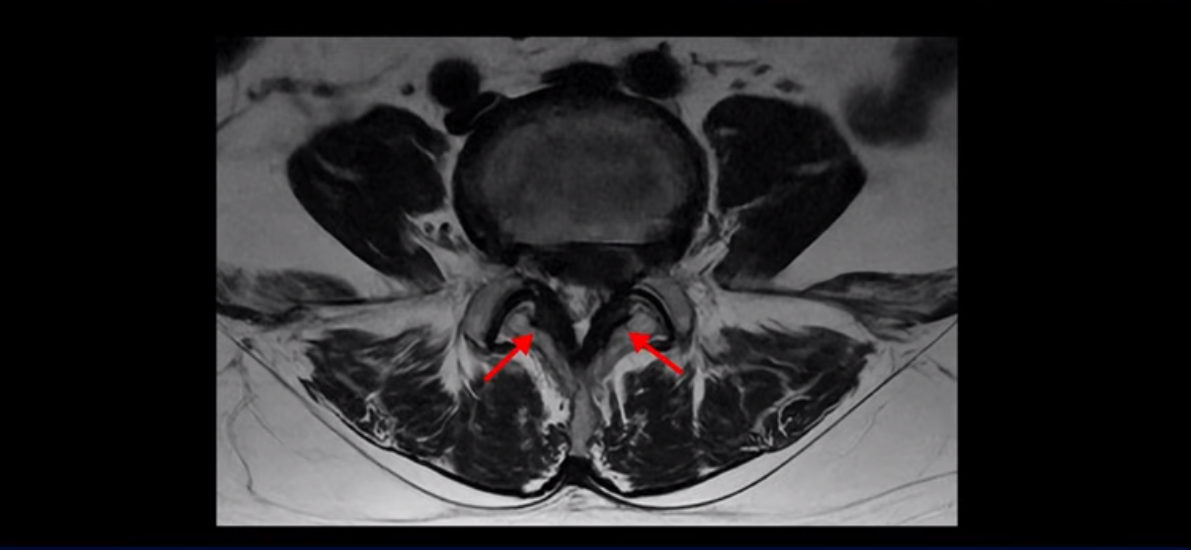

좌우 뒤쪽에는 황색 인대가 두꺼워져 있습니다.

앞에서는 디스크 수핵이 신경 공간으로 침범하고 뒤에서는 두꺼워진 인대가 신경 공간을 좁히고 있습니다.

이렇게 신경 공간이 좁아진 것을 협착이라고 합니다. 왼쪽으로 신경 구멍이 더 좁아져 있으니까 처음에는 왼쪽 엉덩이와 다리가 아팠는데 몇 년 동안 주사 맞으면서 버티다 보니까 오른쪽 다리까지 아프게 됩니다. 결국 양쪽 다리가 너무 아파서 5분 걷기도 힘들어지게 됩니다.